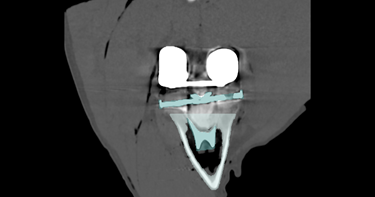

Vanwege de vergrijzing en omdat mensen op jongere leeftijd een eerste (knie)prothese krijgen zullen revisie operaties in de toekomst de Nederlandse gezondheidszorg steeds meer belasten. Goede bevestiging van een revisie (knie)prothese in het omliggende bot is heel belangrijk voor de levensduur van de prothese. Botverlies en een slechtere kwaliteit van het overgebleven bot maakt dit echter lastig. Door voorafgaand aan de operatie de botkwaliteit, hoeveelheid bot, anatomie en reden voor de revisie te onderzoeken, kan een patiënt-specifiek behandelplan worden gemaakt om goede fixatie te bereiken. Of de fixatie goed is, kan vervolgens gemeten worden met 3D CT analyses.